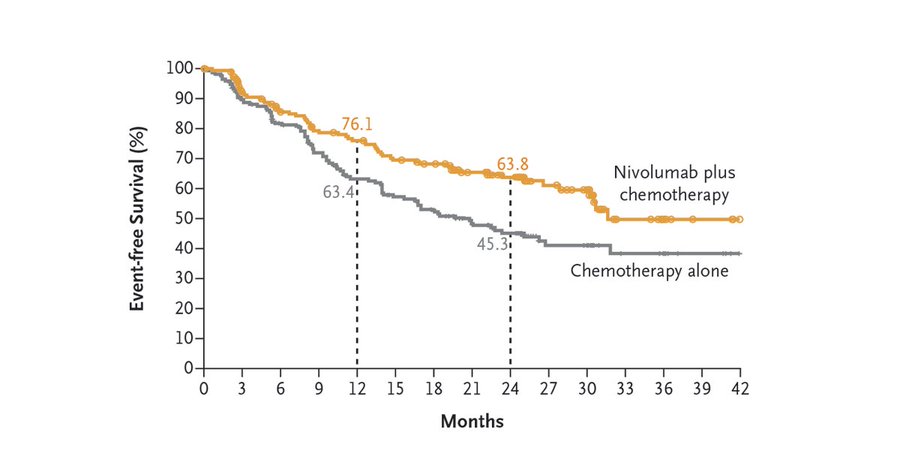

研究人员将患者随机分成两个组:术前接受nivolumab与标准铂类化疗的联合治疗组(179名)和单独化疗组(179名),来观察Nivolumab的联合治疗是否对缩小肿瘤和降低复发风险更有效。

实验结果显示,联合治疗组的无事件生存期平均为31.6个月,化疗组为20.8个月。

与单纯化疗组相比,联合治疗组的无事件生存率明显提高;癌症复发、进展或死亡的风险降低37%。而且,所有癌细胞完全消失,也就是完全缓解(CR)率,联合治疗组(24.0%),明显高于单纯化疗组(2.2%)。美国达纳-法伯癌症研究所的马克-阿瓦德(Mark Awad)是该临床试验的研究小组之一,他说:”完全缓解的患者也都接受了手术,对手术标本进行的病理检查结果显示:只有疤痕组织或纤维化组织,没有活的癌症组织,也没有发现活的癌细胞”。